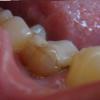

Uliana Опубликовано 5 июня, 2009 Поделиться Опубликовано 5 июня, 2009 Здравствуйте! Имеется проблемная нижняя шестерка. 10 лет назад (в 15 л возрасте) были удалены нервы, поставлены 2 штифта, сверху пломба. До последнего времени конструкция не беспокоила. Полгода назад на шее увеличился лифоузел, недавно поняла, что это скорее всего зуб (т.к лифоузел прямо под зубом). Зуб имеет сероватый оттенок, у шейки розовый (прилагаю фото, кач-во не очень, делала сама)Десна в этом месте отошла, имеется контактный кариес с 2 сторон, пломба просела, трещина на зубе сверху (на фото видно) Из сопутствующих проблем есть гингивит, периодическая чувствительность зубов и аллергия на металлы, кроме золота. Что посоветуете делать? По первости я думала обойтись без коронки, но видимо это не так Единственное пожелание к коронке- ее безопасность для организма. Ссылка на комментарий